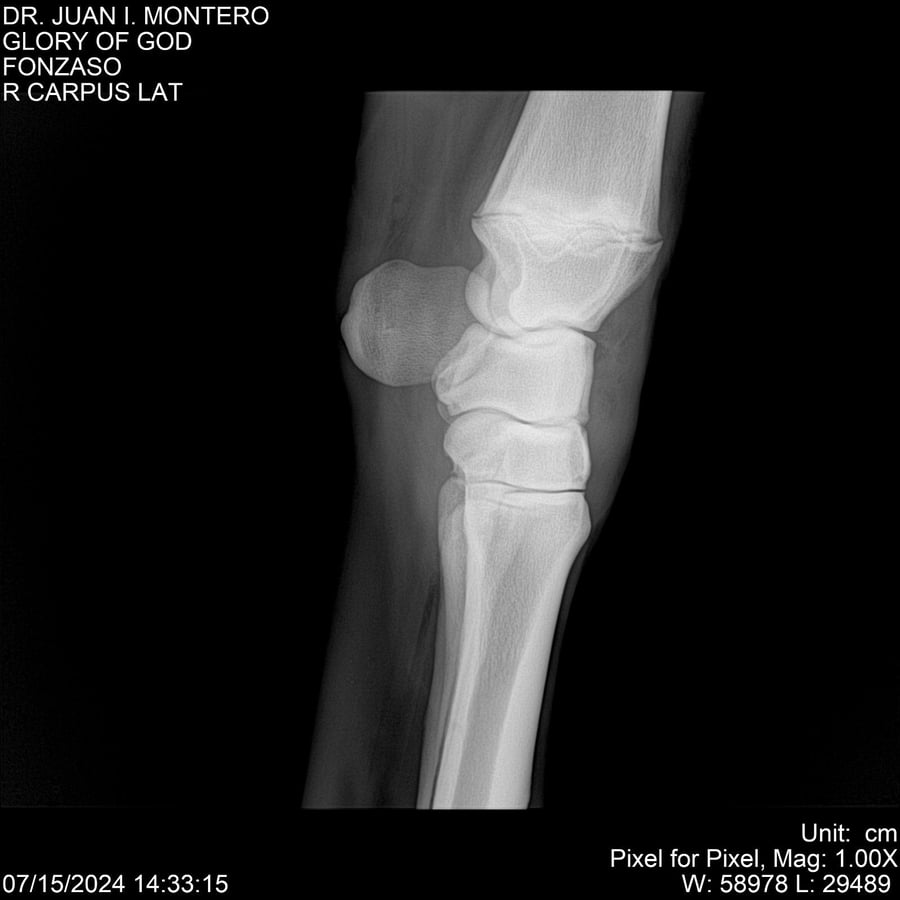

LOTE 10, GLORY OF GOD 🔥 🔥 🔥 Lote Anterior Volver al remate Lote Siguiente Ficha Contacto Montevideo - Ficha del Lote Identificador: #281389 Categoría: Yeguarizos Montevideo - 115 Visualizaciones ClicData Contacto Empresa: Abelenda N. R., Walter Hugo Nombre*: Teléfono* : E-mail* : Mensaje Enviar Registrese gratis Este contenido Exclusivo está disponible sólo para usuarios registrados Ingresar